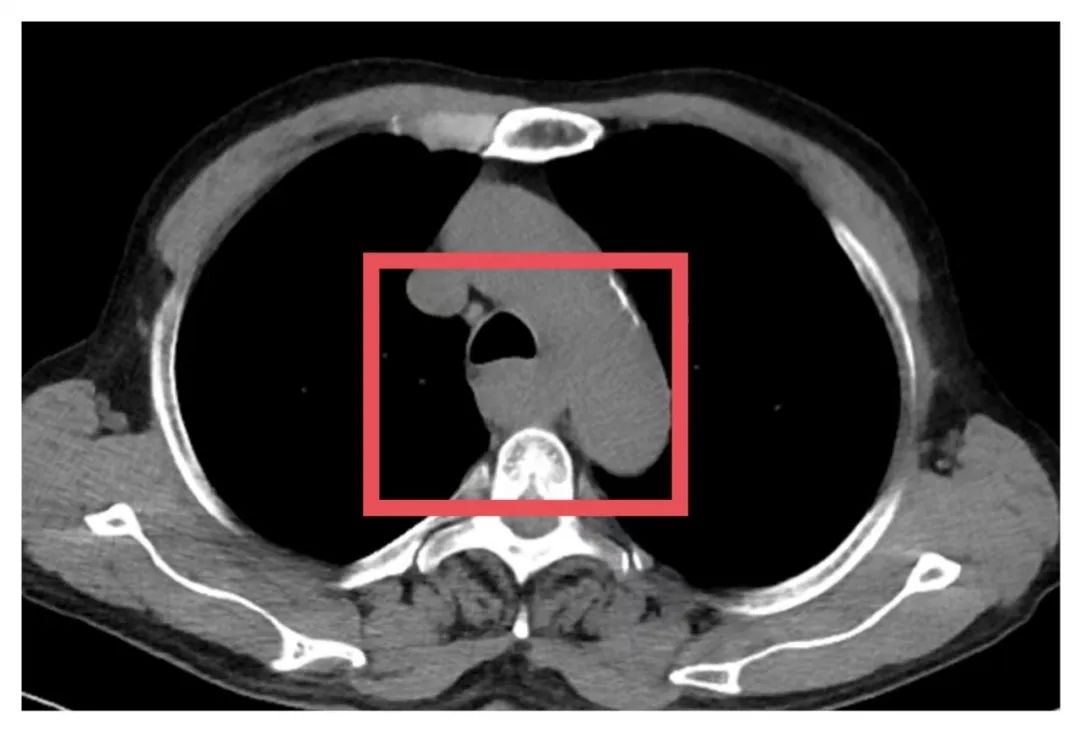

▲患者术前影像学检查

为了争取更大的根治机会,胸外科朱震主任医师为苏先生量身定制定了一套治疗方案——“免疫联合化疗”的新辅助治疗方案,先“软化”肿瘤、减少侵犯,再择期手术。治疗期间,苏先生接受了PD-1单抗与铂类+紫杉醇联合化疗。随着治疗推进,患者主诉症状显著缓解。2025年7月复查CT提示病灶缩小、边界清晰、与周围结构粘连减少,手术时机成熟。

▲患者术前、术后影像对比